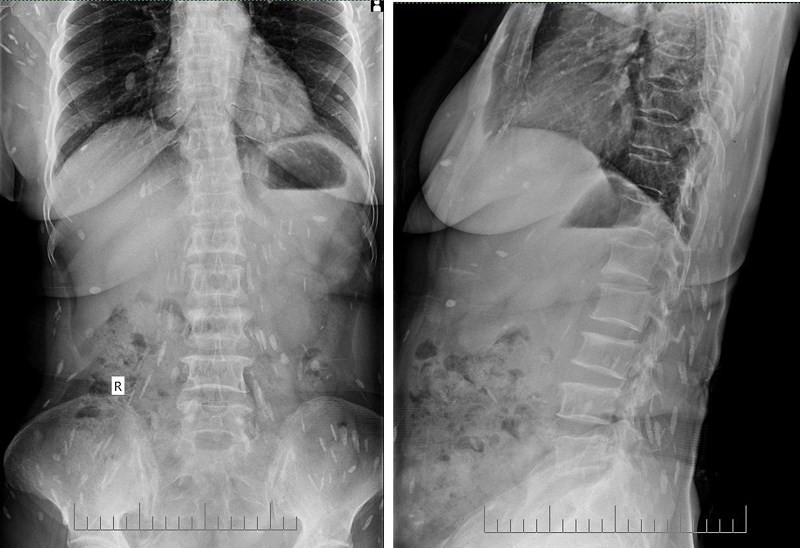

Hình ảnh chụp tim phổi thẳng cho thấy rất nhiều con sán lá gan (màu trắng) ký sinh trong nhiều cơ quan của người phụ nữ. Ảnh: BVCC.